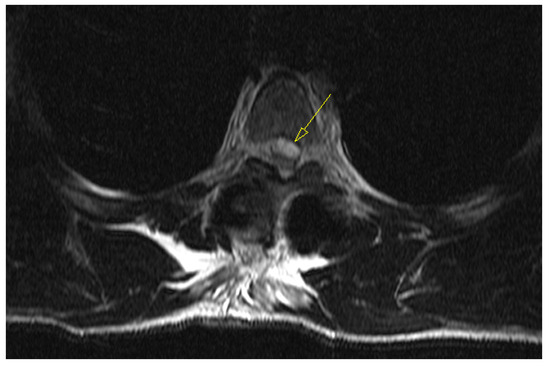

2. Case Report